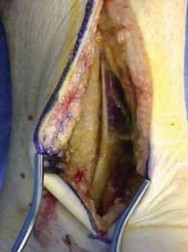

After completing the lateral approach, the surgeon carefully evaluates the lateral process fracture ( TECH FIG 5A,B).

I gently displace the fracture and assess the condition of the subtalar joint.

Small fragments are commonly devoid of soft tissue attachments. Only very small fragments should be removed.

Larger fragments, even those without soft tissue attachments, are needed to restore the structure of the lateral process in any closed fracture of the lateral process of the talus.